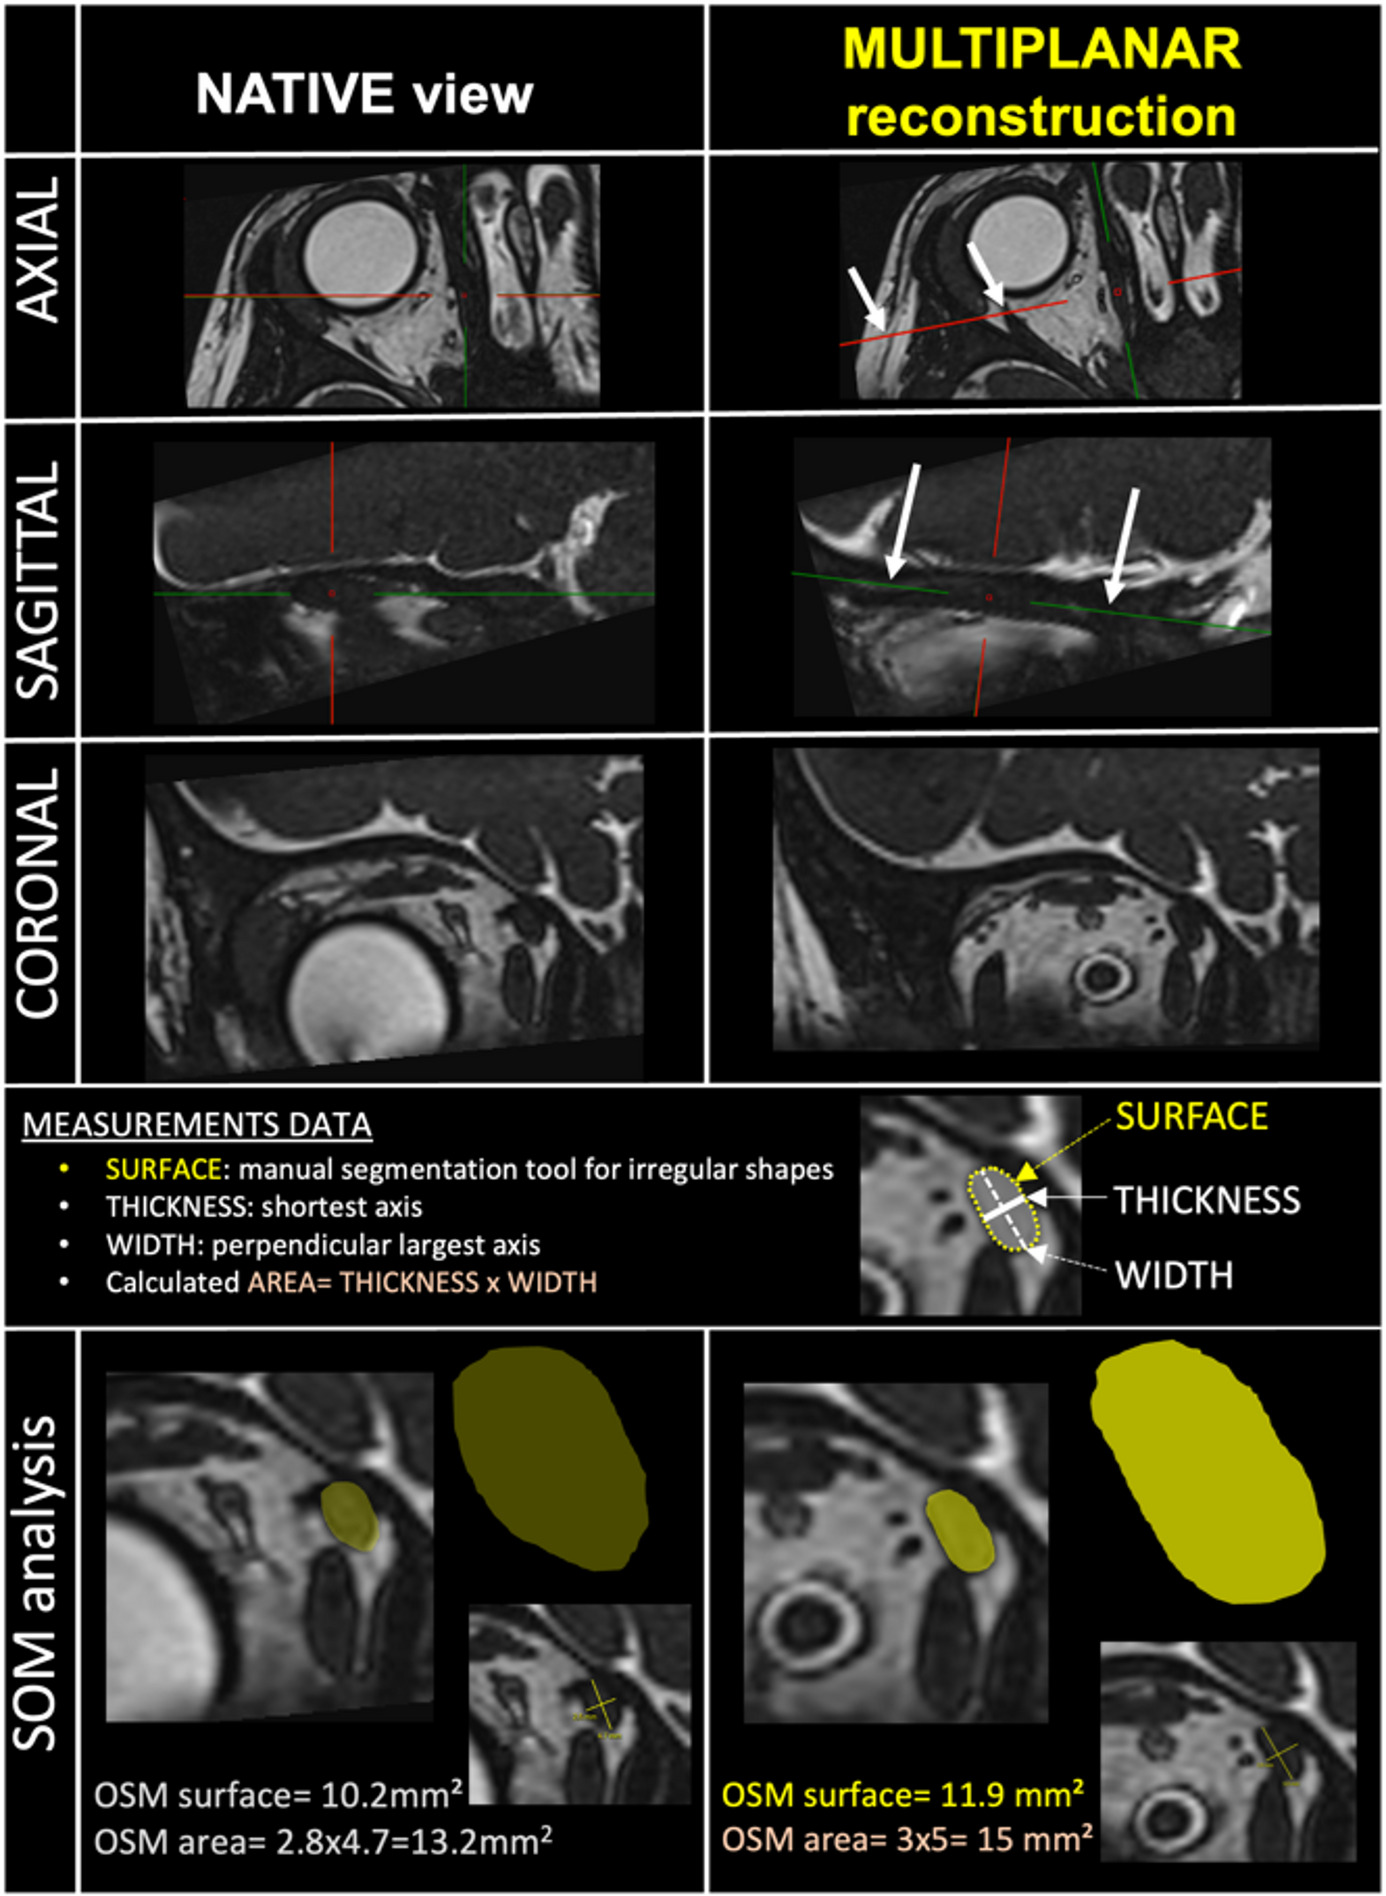

Fig. 1

Magnetic resonance imaging-based assessment of the surface and area of the superior oblique muscle (SOM). Imaging sequence: High-resolution-3D-T2-gradient-echo CISS sequence centered on the SOM. Left column: native view, not used for study measurements. Right column: multiplanar reconstructions - perpendicular (axial view) and longitudinal (sagittal view) along the muscle axis (arrows) using an oblique three-dimensional tool, representing the measurement methodology applied in the study. The coronal muscle section slice is the plane of interest for SOM analysis. SOM analysis row: demonstrates measurement differences between native and reconstructed SOM analysis. Surface measurement: performed using the “irregular region of interest” tool. Area calculation: defined as width (larger axis of the muscle section) multiplied by length (shortest axis).